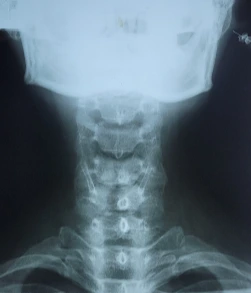

퇴근 후 단골 정형외과 의원에 가서 목 엑스레이 사진을 찍고 함께 보았다.

왼쪽으로 틀어진 나의 목

여전히 꼿꼿한 일자목!!

의사는 "일자목인데 심하지 않네요"

나의 목사진을 보았을 때 옆에서 보면 일자지만 앞에서 볼 때 정렬이 조금 틀어져 보였다.

"그렇네요. 왼쪽으로 약간 틀어져 있네요"